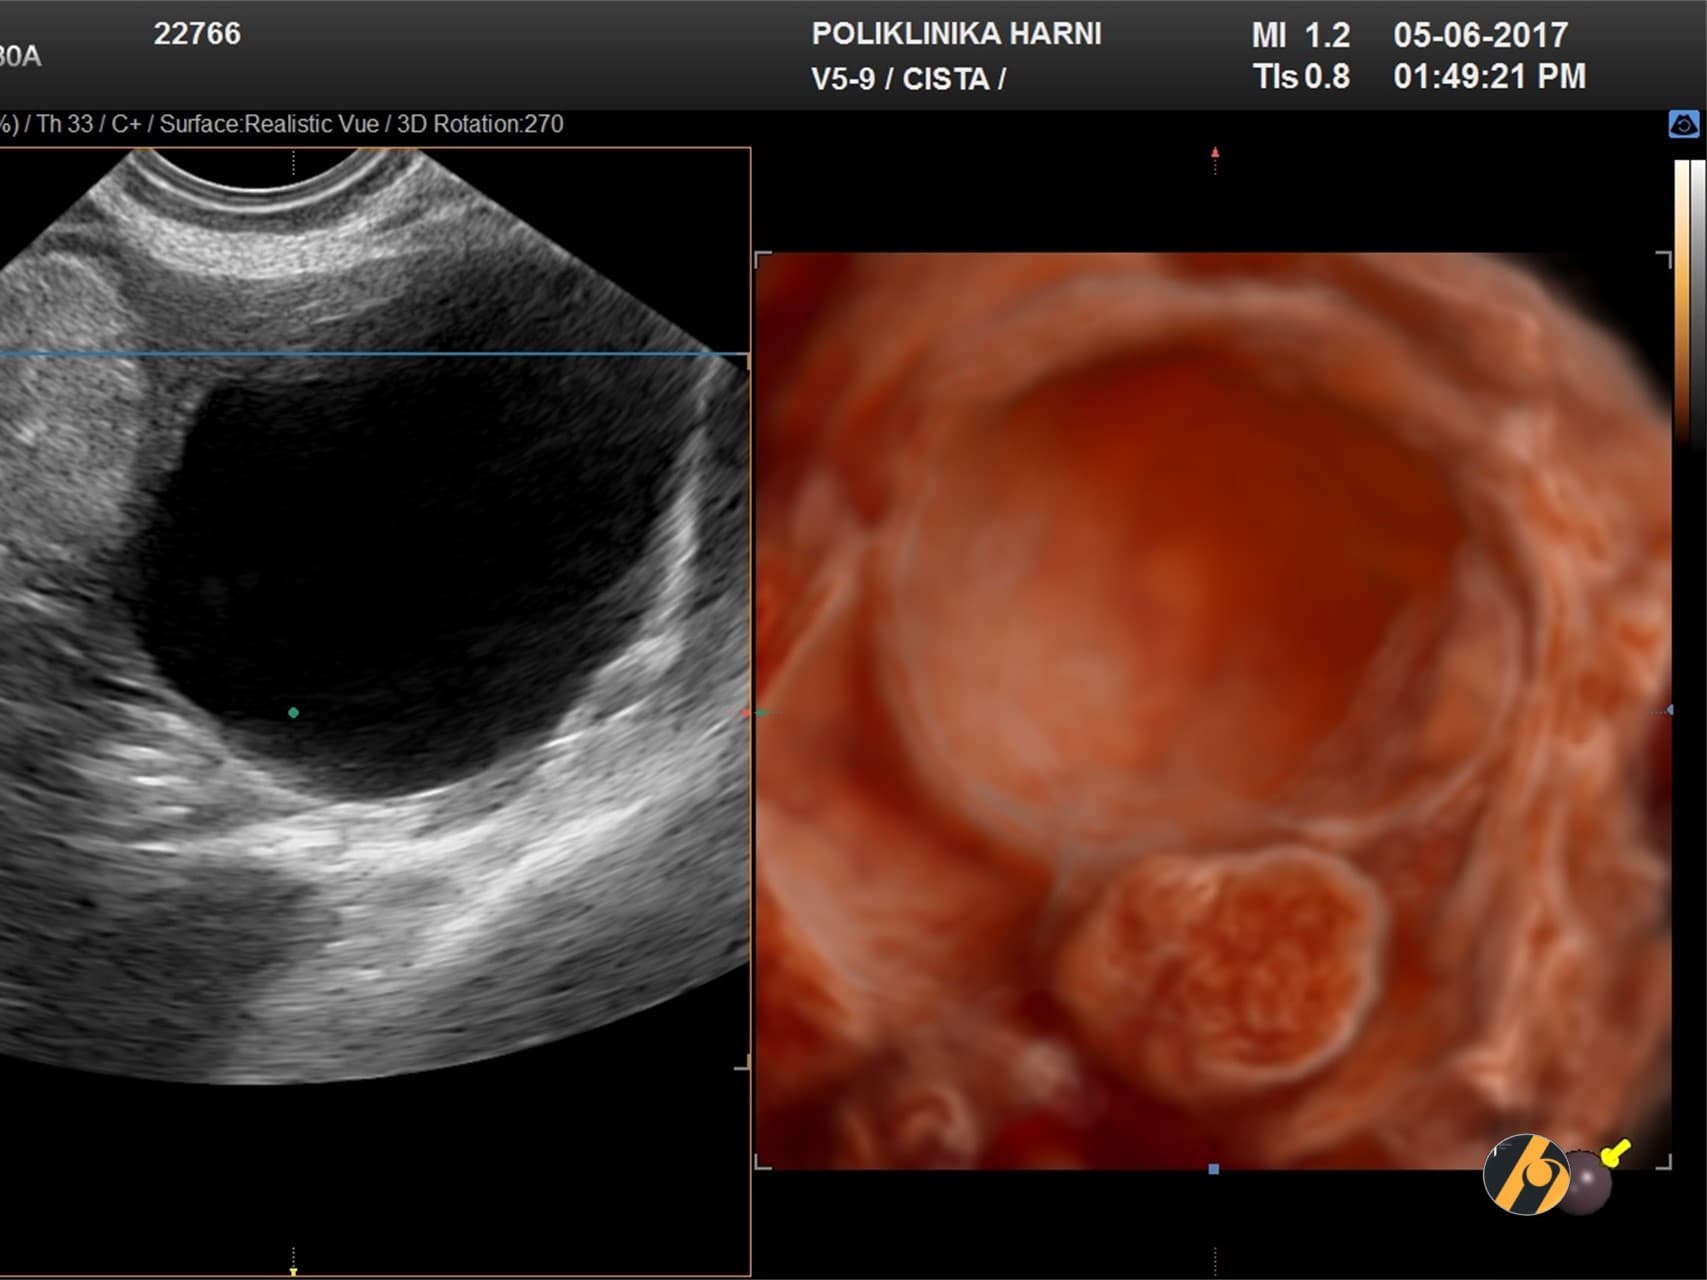

- Zloćudni serozni tumori / cistični karcinomi jajnika. Zloćudne ciste se javljaju kao oblik karcinoma jajnika. Karcinom se javlja kod 20 od 100 000 žena. Zloćudne ciste se razlikuju svojim izgledom od dobroćudnih. Takve ciste obično sadrže više šupljina, izdanke u unutrašnjosti ciste te druge značajke koje mogu upućivati na zloćudni proces.